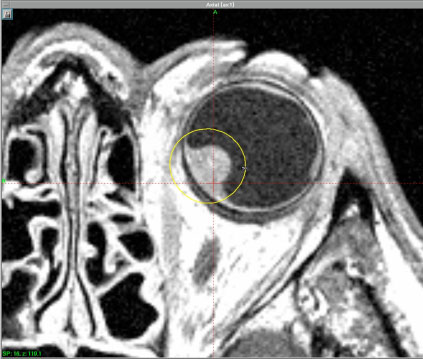

La Gamma Knife è una apparecchiatura complessa, che comprende, oltre l'unità radiante, i sistemi per la localizzazione del tumore, la definizione del piano di trattamento ed il controllo del trattamento.

Il cuore della Gamma Knife è un computer (Gamma Plan) direttamente interfacciato con i più sofisticati sistemi di imaging neuroradiologici (tomografia computerizzata e risonanza magnetica ad alta definizione).

Sullo schermo del computer, al quale giungono direttamente le immagini diagnostiche, l'operatore è quindi in grado di localizzare il tumore, disegnarne i margini, individuare le parti anatomiche da non irradiare, scegliere il collimatore di diametro adeguato alle dimensioni del tumore, calcolare la dose di irradiazione (tempo per numero di shot) ed infine visualizzare le isodosi del trattamento direttamente sull'immagine neuroradiologica.

L'unità radiante contiene 201 sorgenti di cobalto-60 collocate in un corpo emisferico centrale. Il raggio emesso da ciascuna sorgente di cobalto viene accuratamente collimato e fatto convergere con precisione in un punto comune, definito isocentro, corrispondente all'intersezione dei raggi nel centro del casco collimatore. La distribuzione geometrica delle sorgenti e il sistema di collimazione assicurano così dosi elevate all'isocentro, di cui possono essere variate forma e dimensioni, con risparmio dei tessuti perilesionali sani.